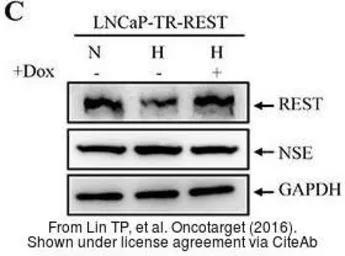

The data was published in the journal Oncotarget in 2016. PMID: 27034167

The data was published in the journal Oncotarget in 2016. PMID: 27034167